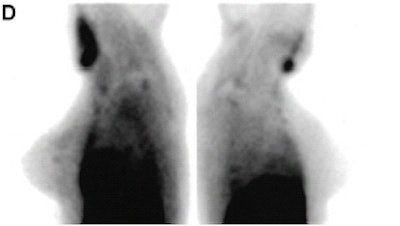

| Images taken with a conventional gamma camera (D) showed possible minimal radiotracer uptake in superior left breast. Biopsy revealed a 4-mm infiltrating ductal carcinoma. Images and captions republished with permission of the Society of Nuclear Medicine from Brem et al, July 2002, Vol. 43:7, pp. 909-915. |